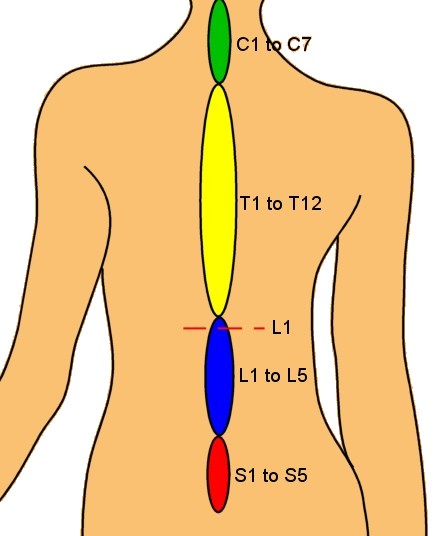

silikonsheet.blogg.se – Spine diagram

Spinal Cord Injury Levels | Bone and Spine | Spinal cord injury, Spinal …

Diagram | Spinal Cord Injury | Pinterest | Spinal Cord Injury and Cords

Diagram showing the relationship between spinal nerve roots and …